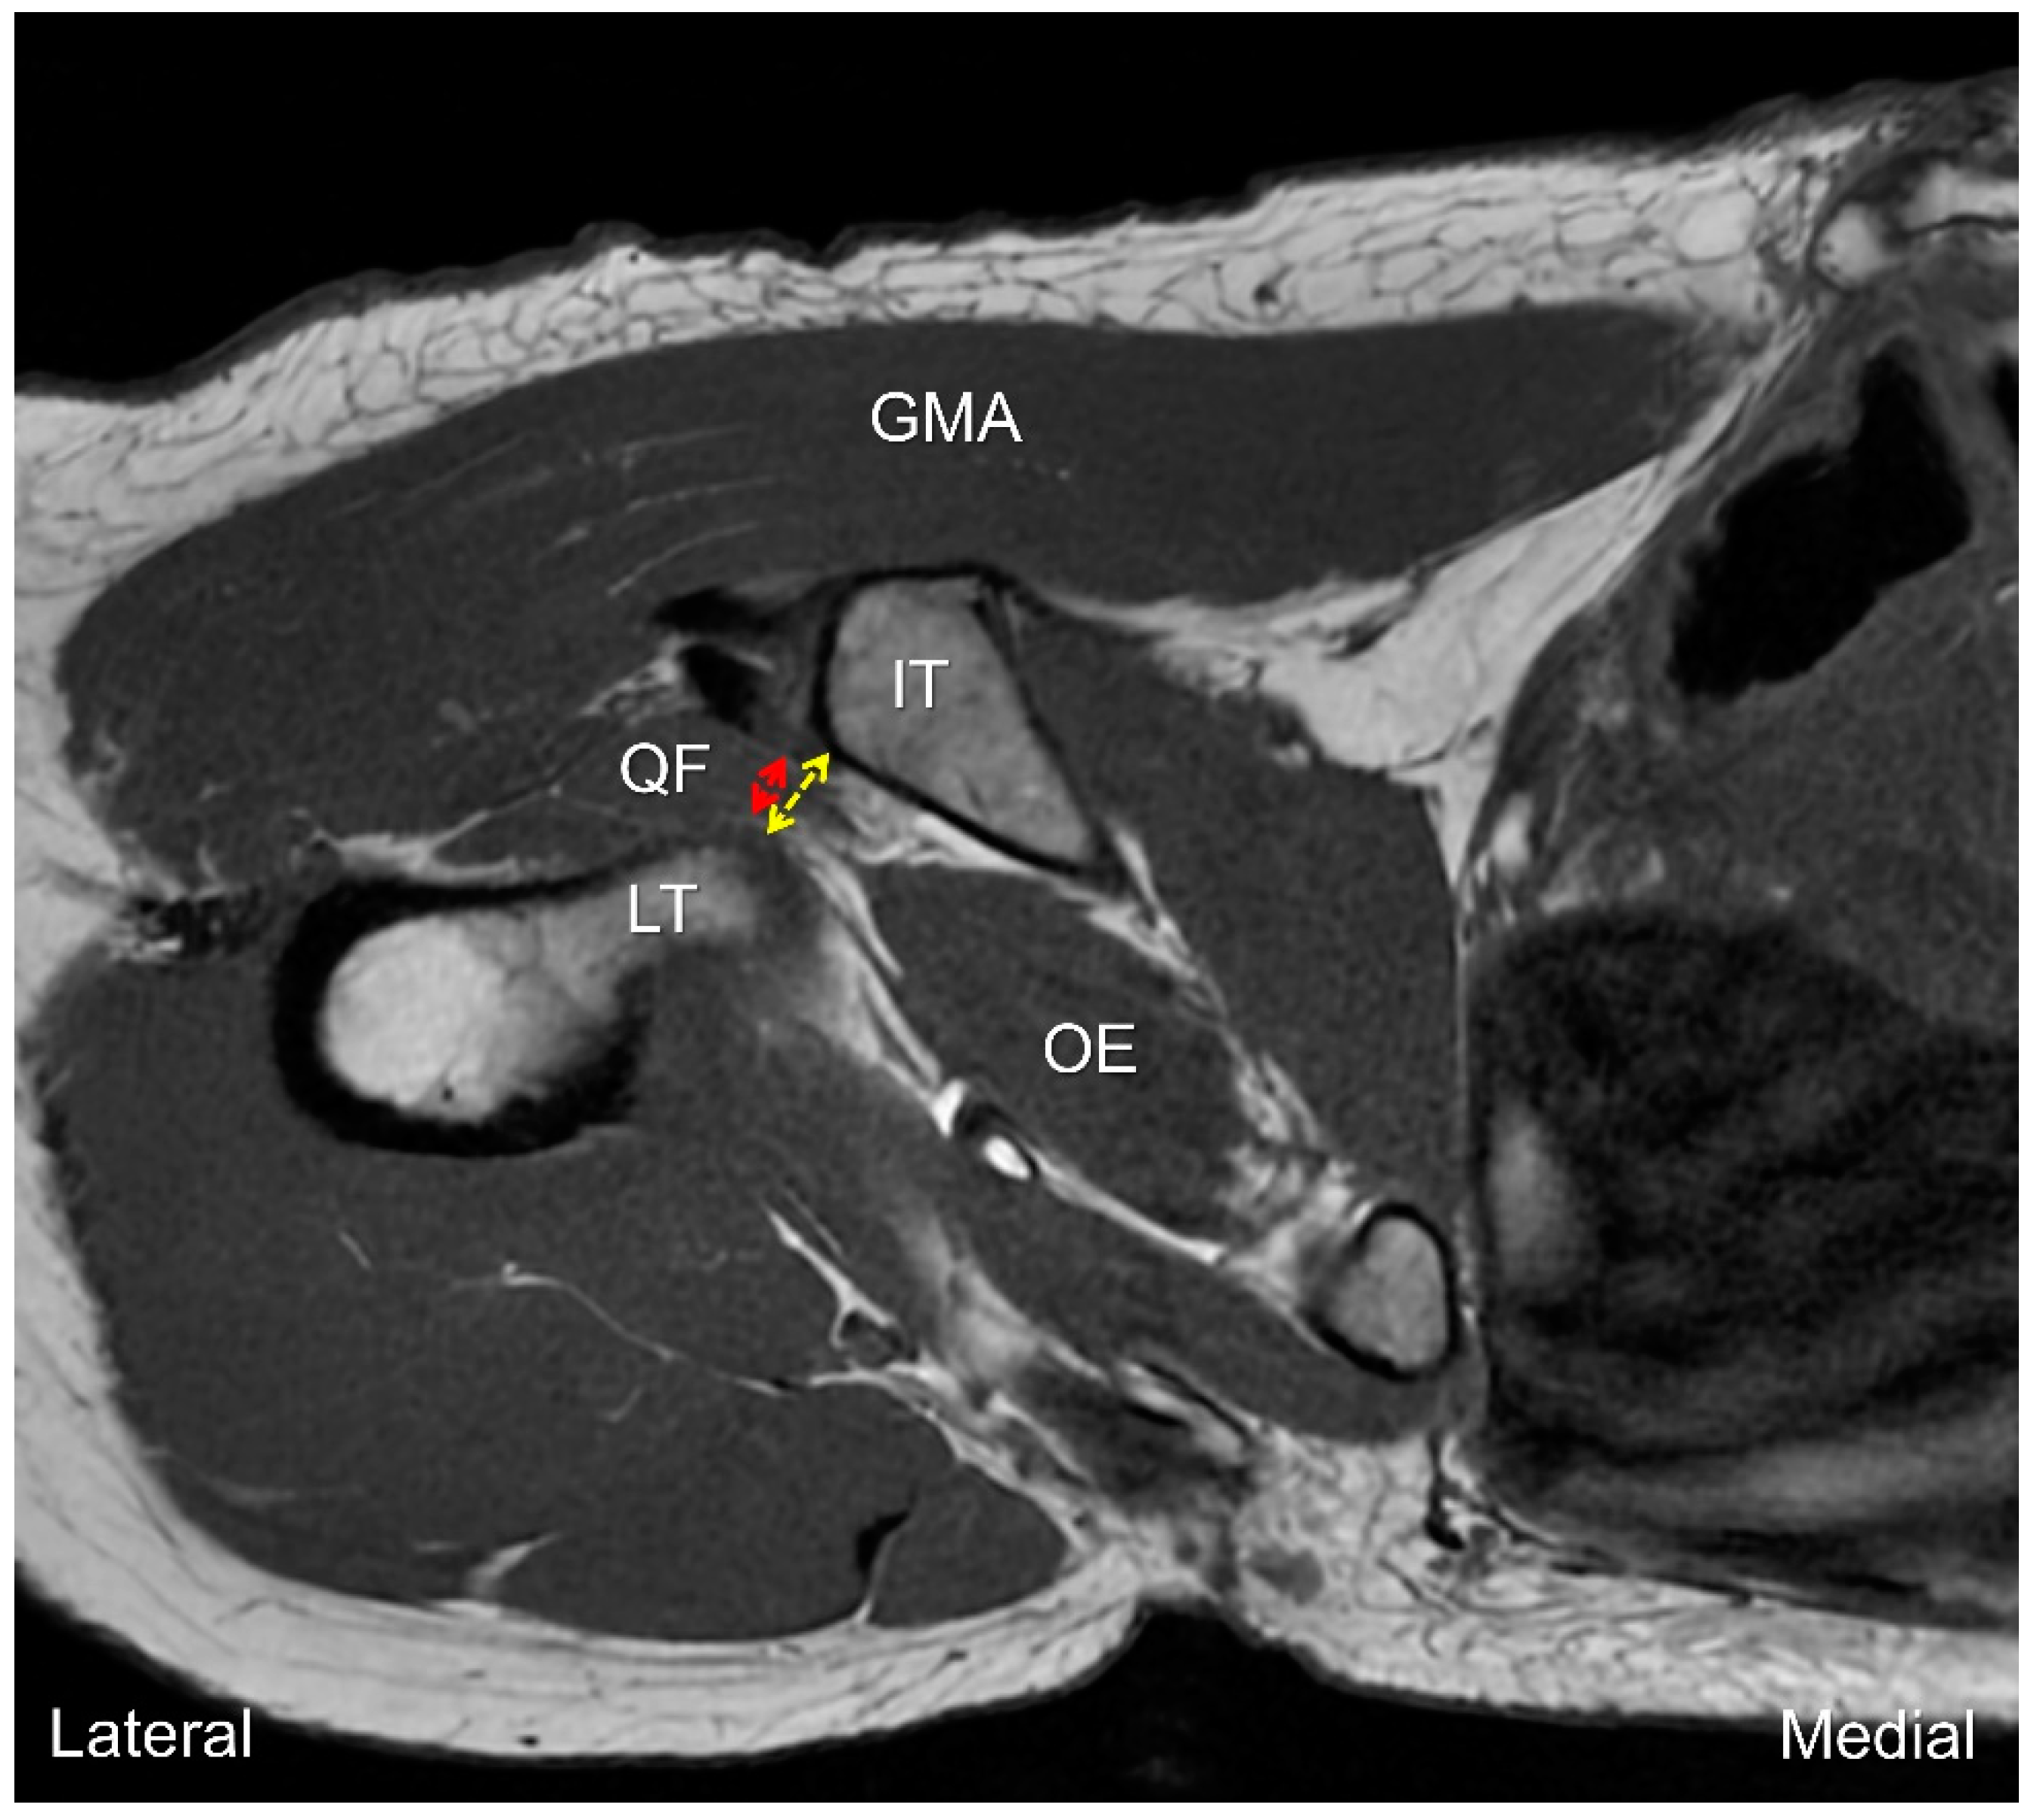

2. Anatomy

7. MRI Assessment

8. Dynamic Ultrasound Evaluation